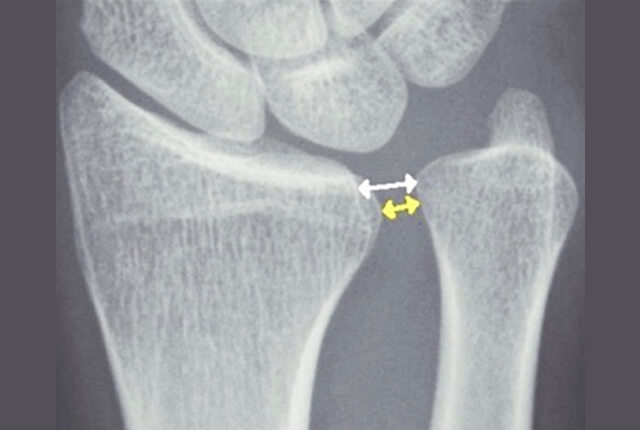

• 単純X線でplus variance

• 単純X線でDRUJの開大

単純X線でDRUJの開大